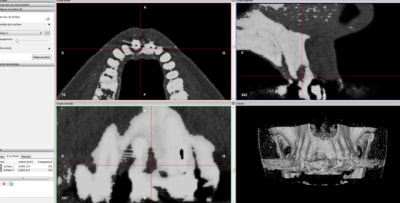

eii rx control faite par confrère à 1an1/2

pas si mal pour un implant léone :-)

ta dent est out alors perso je fais

C'est quoi comme FM, une 360 ou un classique?

Quand je fais des retros de contrôle avec des FM 360, ça n'a pas le même aspect.